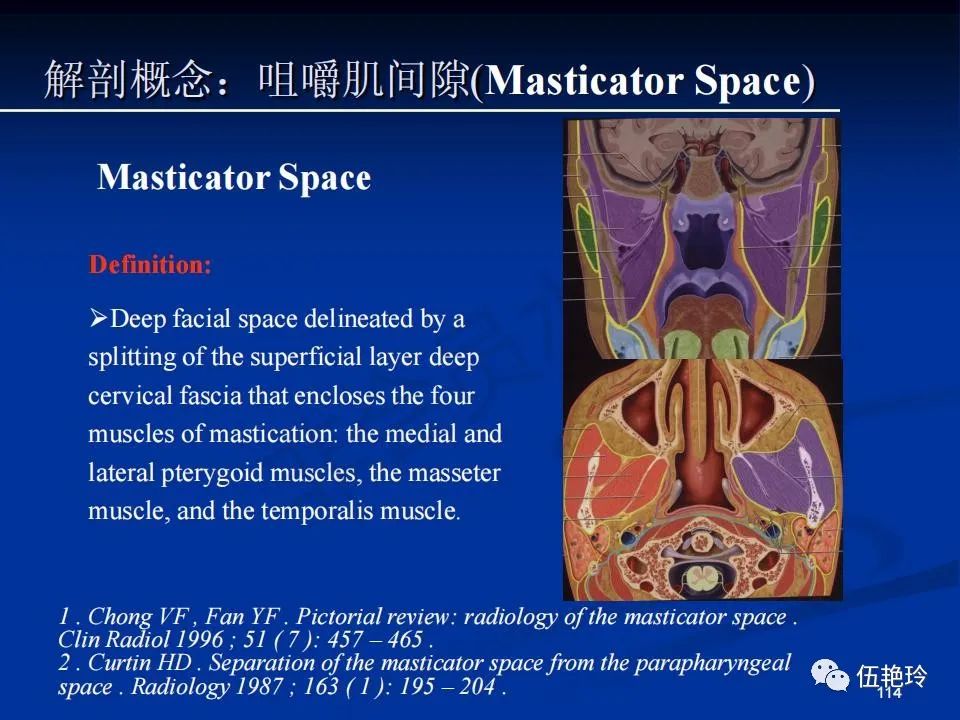

颞下窝与咀嚼肌间隙